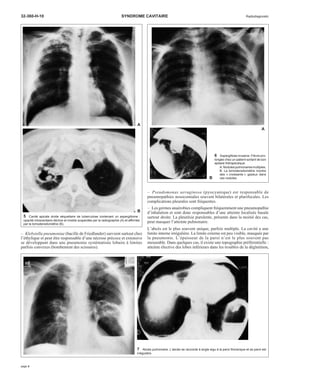

6 Aspergillose invasive. Fièvre pro-longée

chez un patient sortant de son

aplasie thérapeutique.

A. Nodules pulmonaires multiples.

B. La tomodensitométrie montre

des « croissants » gazeux dans

ces nodules.

B

– Pseudomonas aeruginosa (pyocyanique) est responsable de

pneumopathies nosocomiales souvent bilatérales et plurifocales. Les

complications pleurales sont fréquentes.

– Les germes anaérobies compliquent fréquemment une pneumopathie

d’inhalation et sont donc responsables d’une atteinte localisée basale

surtout droite. La pleurésie purulente, présente dans la moitié des cas,

peut masquer l’atteinte pulmonaire.

L’abcès est le plus souvent unique, parfois multiple. La cavité a une

limite interne irrégulière. La limite externe est peu visible, masquée par

la pneumonie. L’épaisseur de la paroi n’est le plus souvent pas

mesurable. Dans quelques cas, il existe une topographie préférentielle :

atteinte élective des lobes inférieurs dans les troubles de la déglutition,